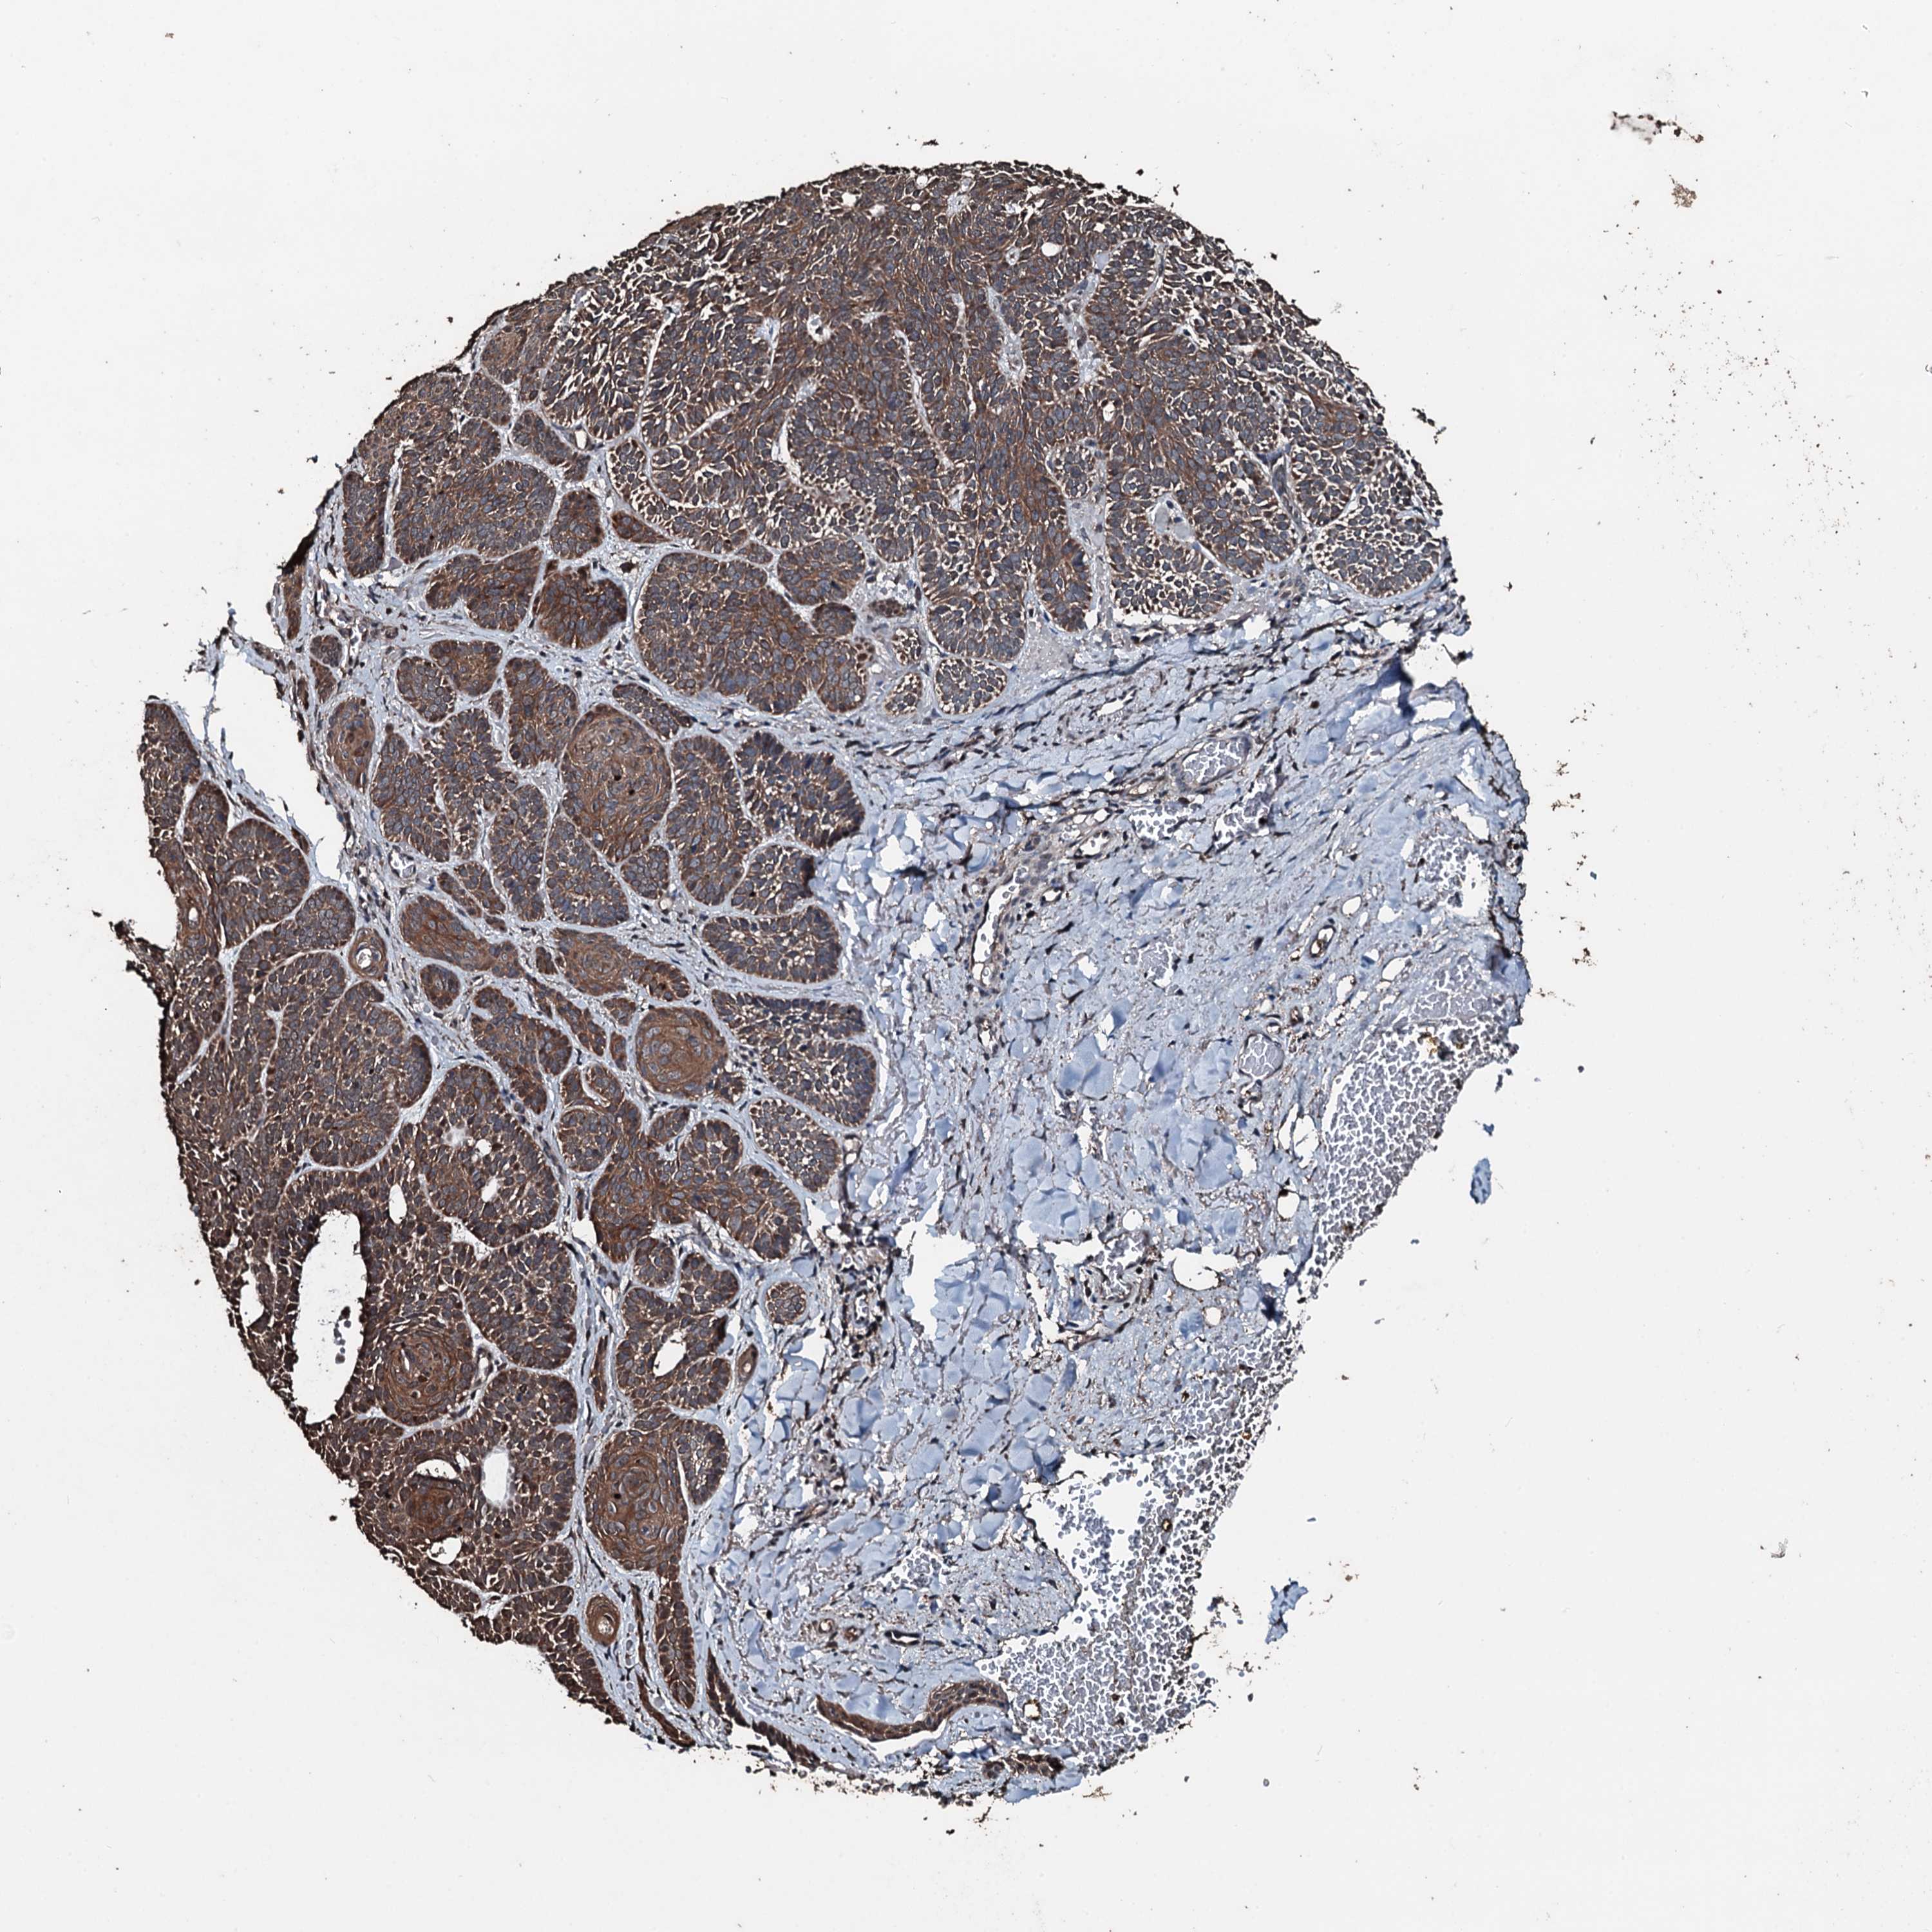

SKIN CANCER - Protein expressioni

A mouse-over function shows sample information and annotation data. Click on an image to view it in a full screen mode. Samples can be filtered based on level of antibody staining by selecting one or several of the following categories: high, medium, low and not detected. The assay and annotation is described here.

Antibody stainingi

Antibody staining in the annotated cell types in the current human tissue is reported as not detected, low, medium, or high, based on conventional immunohistochemistry profiling in selected tissues. This score is based on the combination of the staining intensity and fraction of stained cells.

Each image is clickable and will lead to virtual microscopy that enables deeper exploration of all samples and also displays staining intensity scores, fraction scores and subcellular localization as well as patient and tissue information for each sample.

Antibody HPA041168

Staining

High

Medium

Low

Not detected

Intensity

Strong

Moderate

Weak

Negative

Quantity

>75%

75%-25%

<25%

None

Location

Nuclear

Cytoplasmic/membranous

Cytoplasmic/membranous,nuclear

Basal cell carcinoma

Squamous cell carcinoma, NOS

Squamous cell carcinoma, metastatic, NOS